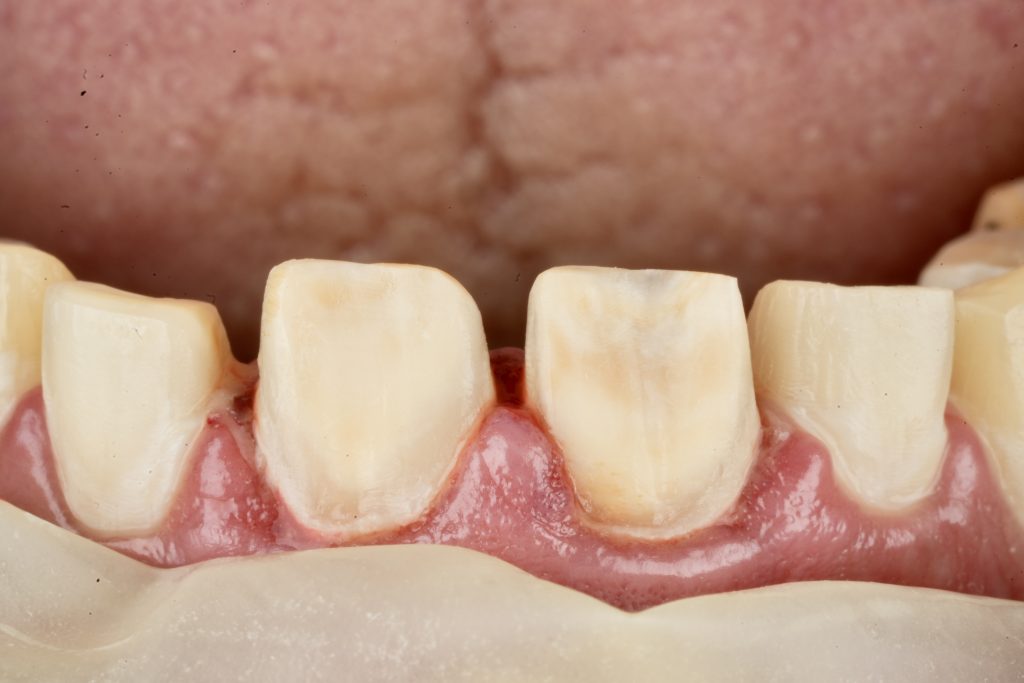

IPS E-max Press veneers were pressed and characterized using micro-layered incisal ceramics for vitality and translucency. Surface texture and internal effects were customized to simulate natural perikymata and halo zones (Fig 3).